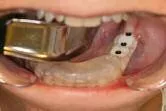

When the patient consents to implant therapy, the restorative or surgical doctor first clinically evaluates the surgical area (Figs. 14a, b) and then refers the patient. If the clinician feels that there is adequate bone volume present to place the implant/implants in the proper position for acceptable esthetic and functional load, then an initial scan is not required.

Clinical evaluation Clinical evaluation